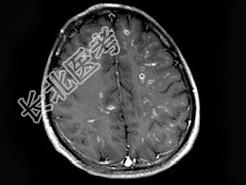

- 单项选择题男,26岁, 头痛、烦躁、意识障碍伴肢体活动障碍数天,头颅MRI检查见多发不规则小条片状结节状强化, 最可能的诊断是 ( )

A、脑结核

B、脑弓形虫病

C、化脓性脑炎

D、多发性硬化